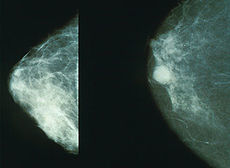

2. RAK NA DOJKI

1. Vznikne

1. Iz tkiva dojke

1. Lobularni karcinom

2. Iz mlečne žleze

1. Duktalni karcinom

3. Zdrava dojka

1. Rakava dojka